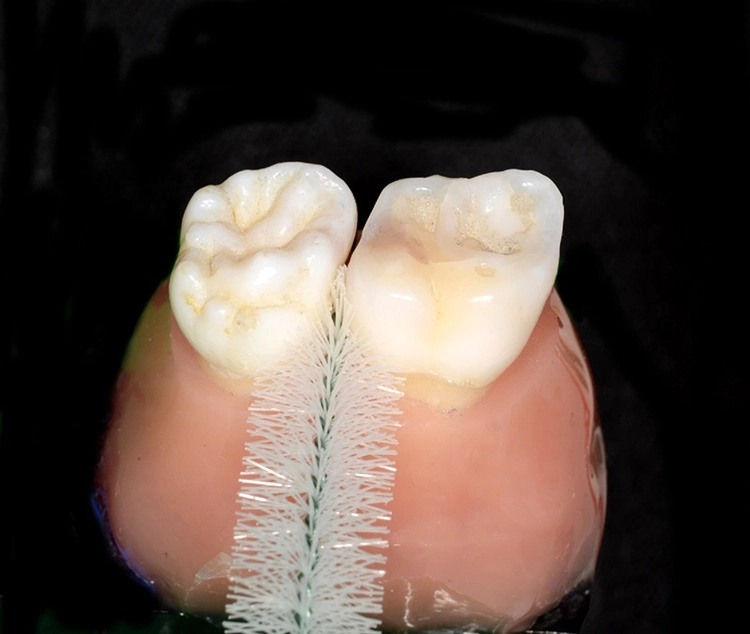

In der Praxis werden an Patienten zuweilen mit Messsonden diverse Größen ausprobiert, um eine entsprechende Empfehlung abzugeben [26]. Allerdings ist ihr Wert umstritten. Eine korrekt angepasste Interdentalraumbürste sollte den kompletten Interdentalraum reinigen und mit „mittlerem“ Druck ein- und auszuführen sein. Wenn sie zu dünn ist, hat sie eine zu geringe Reinigungswirkung; ist sie hingegen zu dick, besteht Traumatisierungsgefahr. Abbildung 2 zeigt die Einprobe und Auswahl am Beispiel des Interdentalraums 41/42.